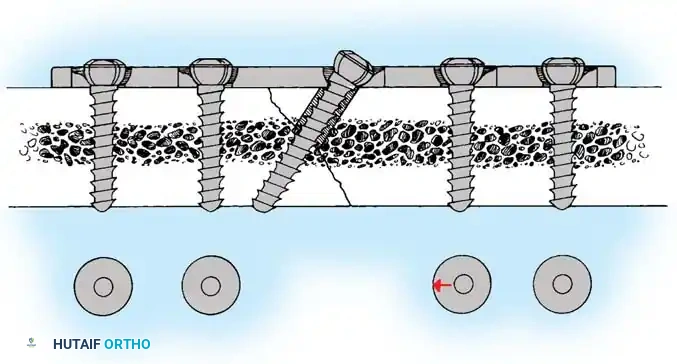

4. Plate Osteosynthesis

If comminution with bone loss prevents the use of a tension band compression technique—due to the risk of shortening the olecranon and narrowing the greater sigmoid notch—plate fixation is mandatory. Plating is also the gold standard for Monteggia fracture-dislocations, oblique fractures extending distally, and fractures involving the coronoid process.

Construct Design:

Hand-contoured reconstruction plates or modern, anatomically precontoured locking plates (e.g., Acumed, Synthes) provide rigid, stable fixation. The plate is applied to the posterior (tension) surface of the ulna.

Clinical Pearl: When applying a posterior plate, use unicortical screws for the holes immediately adjacent to the articular surface to avoid inadvertent penetration into the radioulnar or ulnohumeral joints.

🔪 Surgical Technique: Plate Fixation

- Reduction: Restore the articular block. Temporary K-wires can be used to hold comminuted articular fragments.

- Plate Application: Apply a precontoured olecranon plate to the posterior aspect of the proximal ulna. The proximal portion of the plate often wraps over the tip of the olecranon to capture the proximal fragment with multiple locking screws.

- Fixation: Secure the plate distally to the ulnar shaft using standard cortical or locking screws. If an oblique fracture line is present, a lag screw can be placed independently or through the plate to achieve interfragmentary compression.

- Bone Grafting: If significant metaphyseal void exists after elevating impacted articular fragments, autogenous cancellous bone graft or allograft should be packed into the defect prior to final plate tightening.